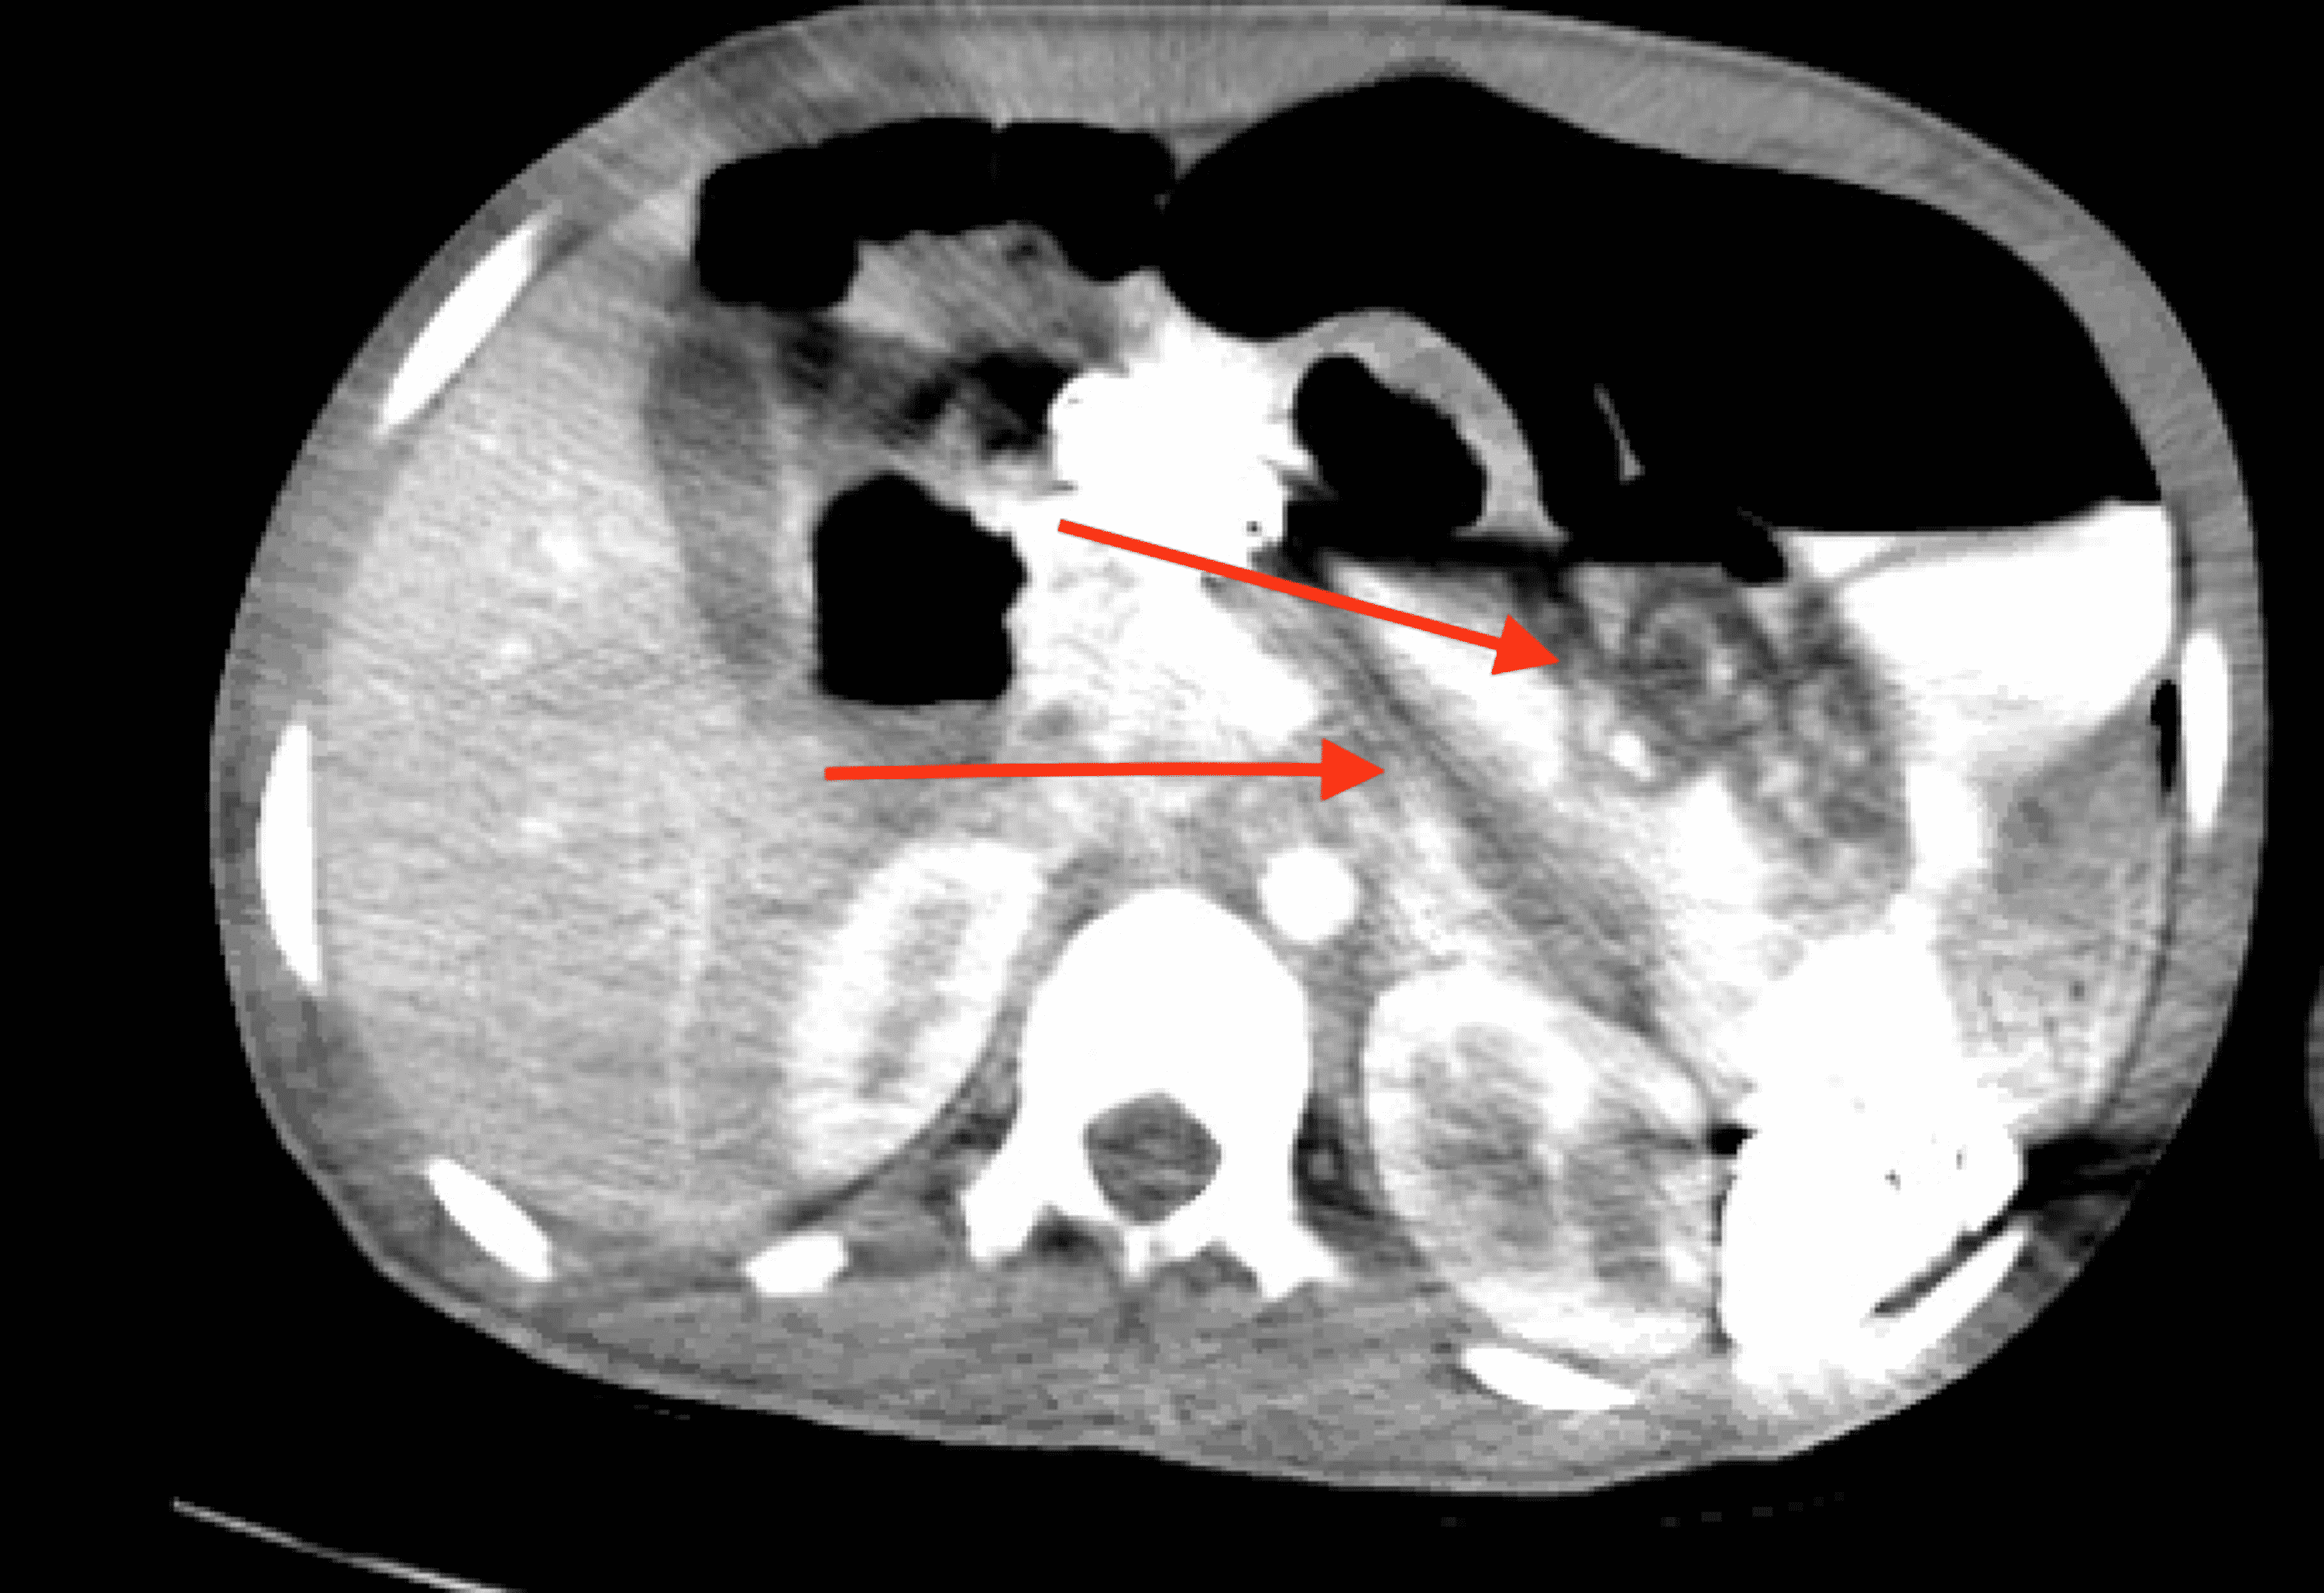

From www.wikidoc.org

Ischemic colitis CT wikidoc Ischemic Colitis Fatal Some people have repeat or chronic episodes of ischemic colitis in one. Ischemic colitis is the most common form of intestinal ischemia. If you have ischemic colitis along with pain on your right side, or sudden belly pain that’s so severe you can’t find a comfortable position, head to. Symptoms are left lower quadrant pain and rectal bleeding. Tissue death,. Ischemic Colitis Fatal.

From www.msdmanuals.com

Image Ischemic Colitis on CT MSD Manual Professional Edition Ischemic Colitis Fatal Ischemic colitis is a transient reduction in blood flow to the colon. Fortunately, with proper medical care, most people diagnosed with ischemic colitis typically recover in a day or two, and never have another episode. Ischemic colitis usually gets better on its own within 2 to 3 days. Tissue death, also called gangrene, resulting. Less commonly, it can be a. Ischemic Colitis Fatal.